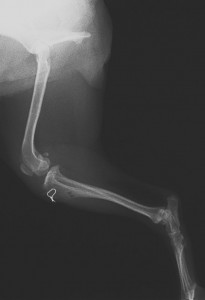

上腕骨粉砕骨折 脛骨近位骨折

脛骨遠位骨折 大腿骨骨折